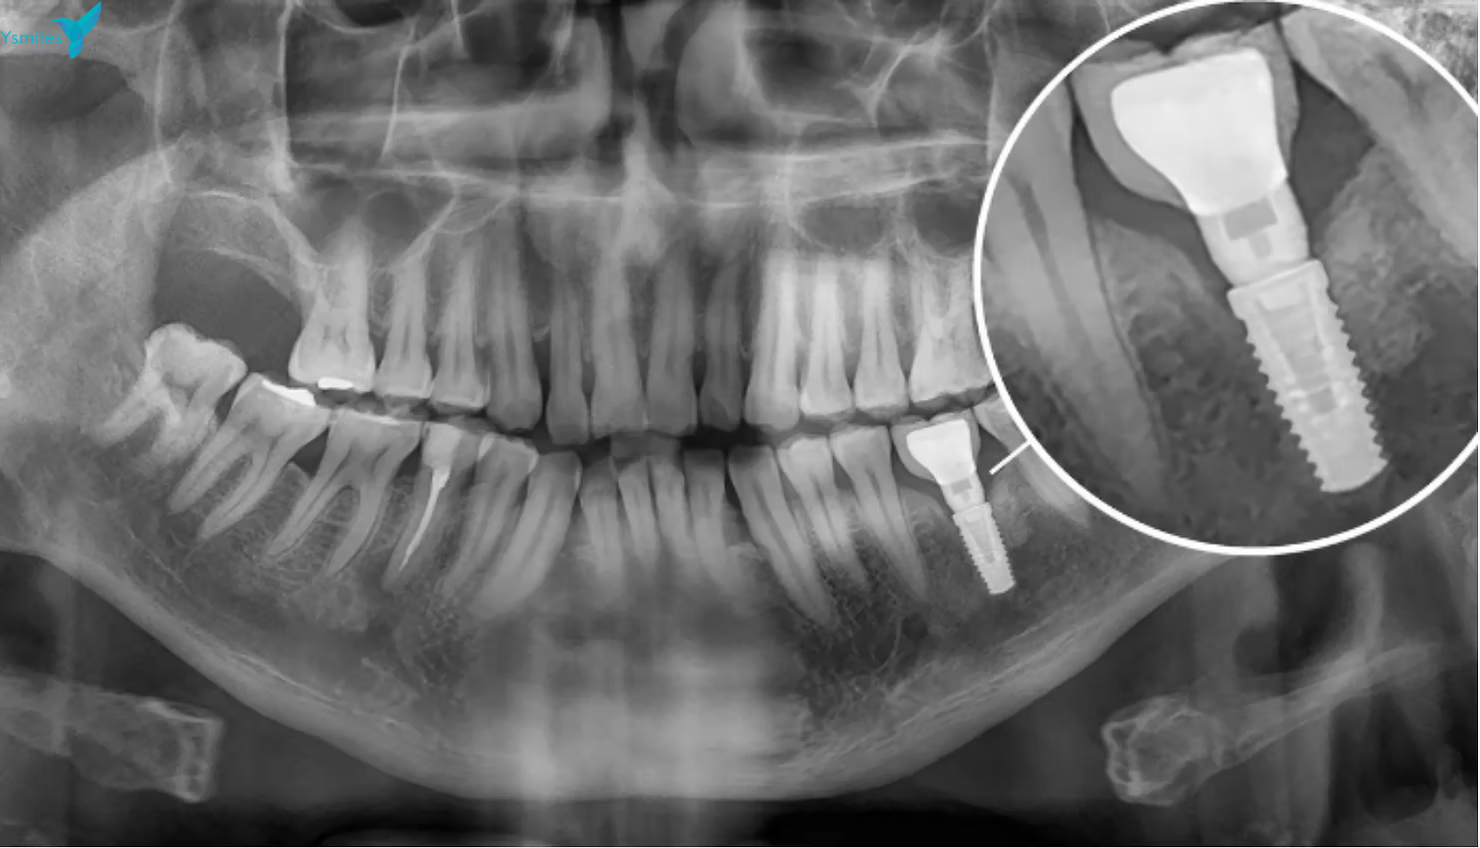

A dental implant is a small, titanium post that acts as an artificial tooth root. It is surgically placed into the jawbone, where it fuses over time, providing a strong and stable foundation for a replacement tooth, bridge, or denture.

2. Implant Placement: The titanium post is surgically placed into your jawbone. This procedure is performed with local anesthesia to ensure you are comfortable.

3. Healing Period (Osseointegration): The implant is left to heal and fuse with the bone, a process that typically takes a few months.

4. Abutment and Crown Placement: Once the implant is fully integrated, we attach a connector (abutment) and then place your custom-made crown, bridge, or denture on top.